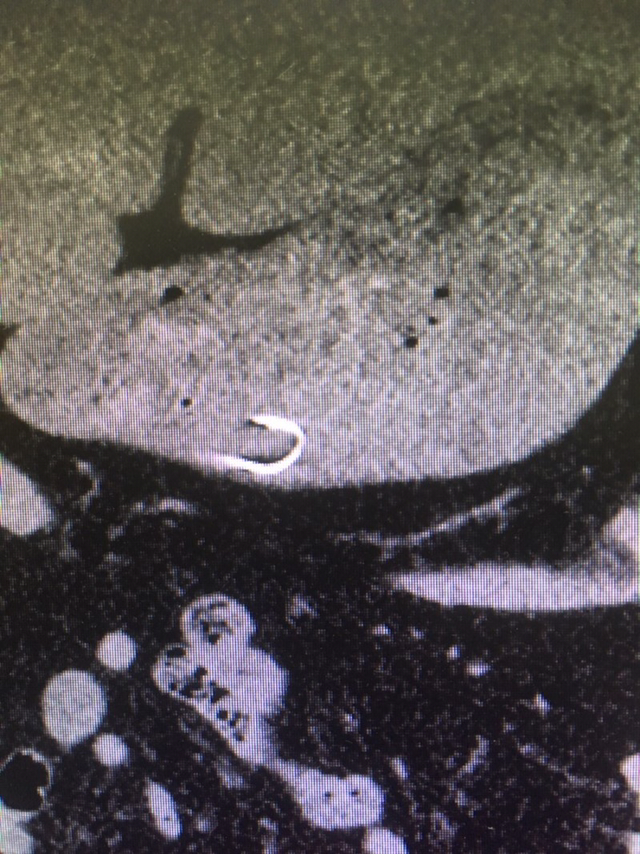

배가 아프다며 한 사내가 ER에 들어선다. 체했겠거니 생각하고 일단 통증부터 다독인다. 이어, 범인 색출에 돌입한다. 어라, 배 사진이 심상치 않다. 갈치를 뼈까지 꿀꺽 삼켰다더니, 명치 부근에 갈고리 철사가 똭!

천공을 우려하며 복부 CT까지 살핀다. 몸 웅크린 철사가 아슬아슬하게 위벽에 붙어 있다. 일이 더 커지기 전에 내시경 시술. 불청객을 소우주 밖으로 축출한다. 철사의 정체는 낚시 바늘.